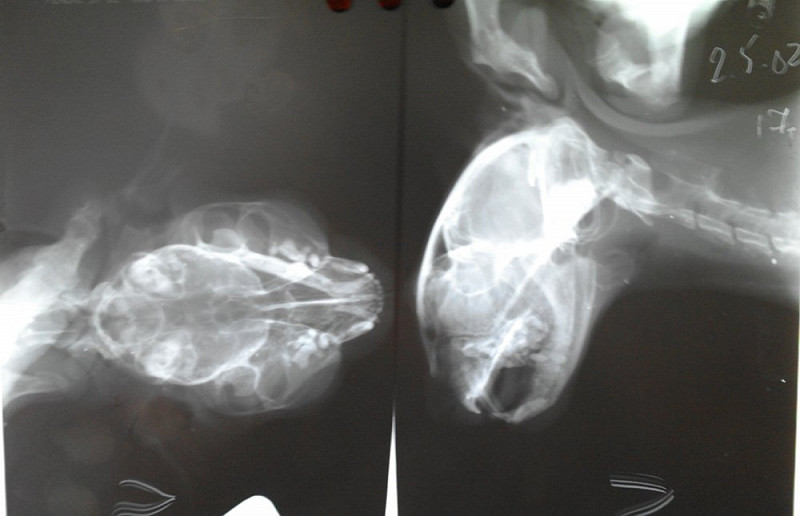

Рентгенологическая диагностика саркомы у кошек

Раздел: Визуальный дайджест